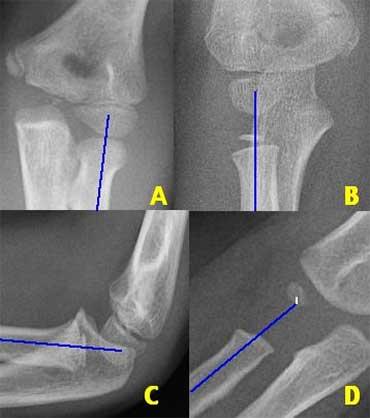

Có hai đường quan trọng giúp chẩn đoán trật khớp và gãy xương.

Đó là đường Quay-Chỏm (Radiocapitellar) và đường Cánh tay trước (Anterior humeral).

Đường quay-chỏm

Một đường kẻ qua trung tâm cổ xương quay phải đi qua trung tâm của chỏm con, bất kể tư thế của bệnh nhân như thế nào, vì xương quay khớp với chỏm con (hình minh họa).

Trong trường hợp trật xương quay, đường này sẽ không đi qua trung tâm của chỏm con.

Ở bên trái, chúng ta thấy rằng đường quay-chỏm đi qua trung tâm của chỏm con trên mọi phim X-quang, mặc dù C và D không ở tư thế chuẩn.

Lưu ý gãy xương trên lồi cầu ở hình B.

Bên trái là các ví dụ khác về đường thẳng quay-chỏm.

Hình ảnh phía dưới bên phải cho thấy sự trật khớp rõ ràng của xương quay.

Radiographs of elbows at different ages. The Anterior Humeral line goes through the middle third of the capitellum .

Đường Humeral trước.

Một đường kẻ trên phim chụp nghiêng dọc theo bề mặt trước của xương cánh tay phải đi qua một phần ba giữa của chỏm con.

Đường này được gọi là đường Humeral trước.

Trong các trường hợp gãy xương trên lồi cầu, đường Humeral trước thường đi qua một phần ba trước của chỏm con hoặc ở phía trước chỏm con do sự uốn cong ra sau của đoạn xương cánh tay xa.

Ở bên trái, đường thẳng cánh tay trước đi qua một phần ba trước của chỏm con.

Điều này cho thấy các lồi cầu bị di lệch về phía sau (tức là gãy trên lồi cầu).